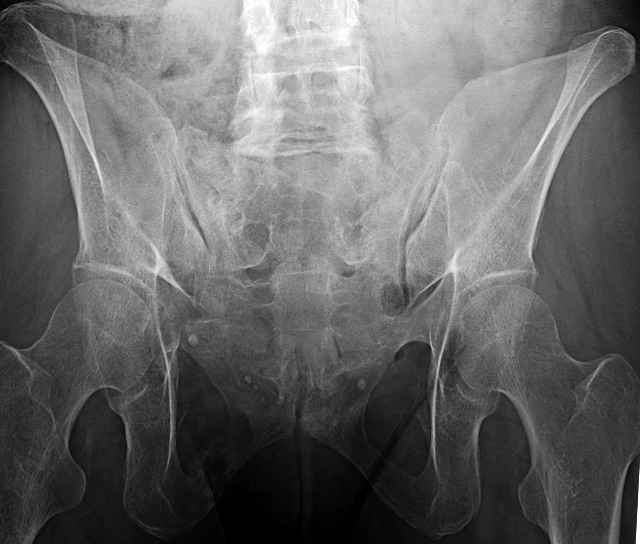

Here are a recent patient’s example slides...

54 yo Female Fell c/o Pain

Initial Films

3 Months After Fall

Continued Pain & Immobility

(+) Instability to Compressive Manual Exam

Pelvic CT Scan - 3 Months After Fall

Sacral Injuries

Ramus Fractures